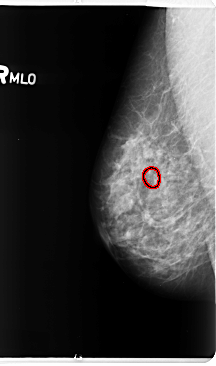

B_3145_1.RIGHT_MLO

RIGHT_MLO LINES 4752 PIXELS_PER_LINE 2808 BITS_PER_PIXEL 12 RESOLUTION 50 OVERLAY

FILE: B_3145_1.RIGHT_MLO.OVERLAY

TOTAL_ABNORMALITIES 1

ABNORMALITY 1

LESION_TYPE CALCIFICATION TYPE PLEOMORPHIC DISTRIBUTION CLUSTERED

ASSESSMENT 4

SUBTLETY 4

PATHOLOGY BENIGN

TOTAL_OUTLINES 1

BOUNDARY